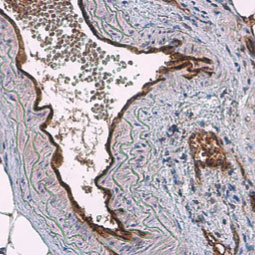

GeneTex is proud to offer an extensive line of research antibodies to support the study of angiogenesis. Please see the highlighted products below or click the button to see more product information.